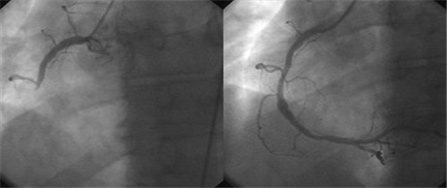

冠状动脉是随着围绕心脏的外侧, 供应心脏氧气和营养而维持心脏的功能的重要血管。冠状动脉疾病是此血管因粥状动脉硬化症而出现狭窄导致心脏肌肉的血流供应产生障碍,因此出现胸痛或呼吸困难等症状,严重时可能出现心脏麻痹、死亡。

冠状动脉疾病在西方已很久以前开始成为最常见的死亡原因,此外,最近在韩国随生活像西方化,其出现频率急剧增加趋势,其重要性和严重性日益凸显。

心脏的冠状动脉中发生粥状动脉硬化会导致血管变窄引起血流不通畅、心脏肌肉出现缺氧现象。氧气供应有限的情况下,肉体活动增加的氧气需求无法满足供应量而出现胸口疼痛,休息的情况下会慢慢好转。 胸痛大部分15分钟以内持续,休息或甘油三硝酸脂放到舌头底下会好转。除此之外,特别在年轻的年龄层中常发生,也会在晚上或凌晨发生变异型心绞痛。